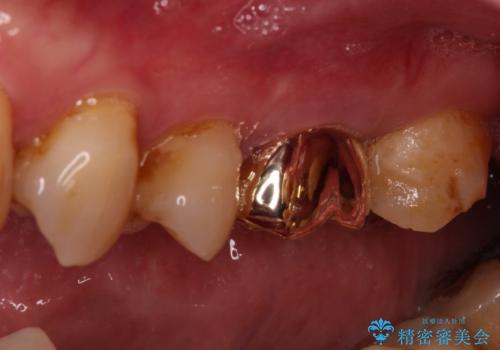

強い咬合力により歯が破折したため、補綴物は歯へのダメージの最も少ないゴールドクラウンを選択しました。